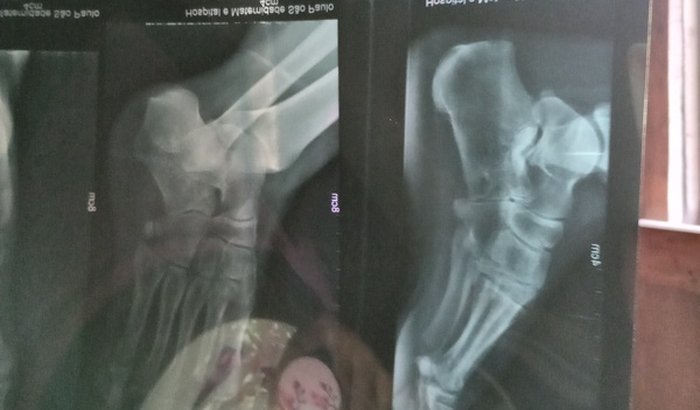

Eu sou a Karina fiz essa vaquinha para arrecadar 16500 pra fazer minha cirurgia no pé artrodese vascular não tenho condições de paga por isso criei essa vaquinha 069999616296 esse é meu zap caso alguém quiser ver meus laudos meus raio x tbm essa é minha conta pessoal tbm se prescisa caso vocês querem ajuda agência 2783